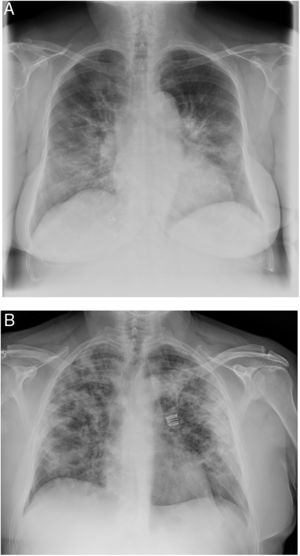

Cuando la imagen radiológica es anormal existen algunos patrones comunes31. En la radiografía simple de tórax se identifican zonas asimétricas de opacidad alveolar o intersticial, parcheadas o difusas. El patrón más habitual es el de neumonía bilateral, con opacidades en vidrio deslustrado subpleurales, con márgenes poco definidos y una ligera predilección por el lóbulo inferior derecho (fig. 1).

Ejemplos de radiología de tórax simple de pacientes con neumonía en contexto de COVID-19.

A. Neumonía moderada, con consolidaciones retículo-alveolares en campos medios e inferiores bilaterales. B. Neumonía grave, afectación extensa bilateral con opacidades alveolares, con tendencia la consolidación en la periferia de ambos campos pulmonares.

Los hallazgos más característicos en la TAC torácica son opacidades múltiples en vidrio deslustrado con consolidaciones en la periferia del pulmón32. Si se identifican estos hallazgos atípicos (incluso en pacientes asintomáticos) se debe considerar el diagnóstico de COVID-19. La estratificación por TAC se ha utilizado para evaluar la gravedad, y es la prueba diagnóstica más sensible, ya que detecta lesiones que a veces no se identifican en la radiografía simple de tórax. Esto puede ser especialmente relevante en la identificación precoz de casos, por ejemplo de forma preoperatoria en pacientes con sospecha que requiriesen intervención.